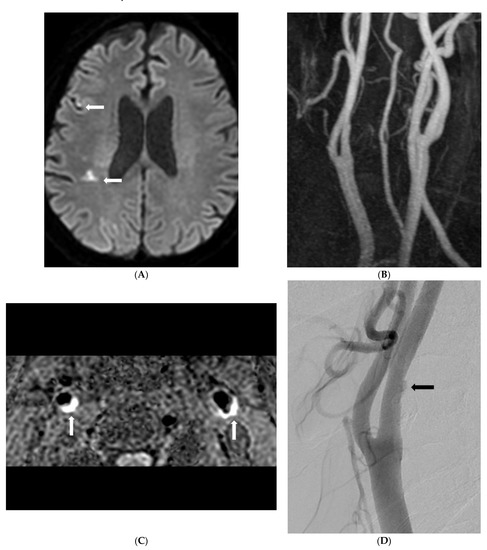

Background: To determine the prevalence of symptomatic nonstenotic carotid disease (SyNC) using simultaneous non-contrast angiography and intraplaque hemorrhage (SNAP) imaging for patients with acute stroke as an MR screen protocol and to assess imaging findings of carotid plaques. Patients and Methods: From May [...] Read more.

Background: To determine the prevalence of symptomatic nonstenotic carotid disease (SyNC) using simultaneous non-contrast angiography and intraplaque hemorrhage (SNAP) imaging for patients with acute stroke as an MR screen protocol and to assess imaging findings of carotid plaques. Patients and Methods: From May 2020 to October 2021, 2459 patients with suspected acute neurological symptoms were evaluated with brain diffusion-weighted imaging (DWI) and carotid SNAP imaging. We analyzed the degree of stenosis and intraplaque hemorrhage (IPH) using SNAP imaging. Prevalence of SyNC and risk factors for stroke in patients with SyNC were determined. We performed subgroup multivariate analysis between SyNC and other etiologies of stroke (non-SyNC). Results: Of 4608 carotid arteries in 2304 patients enrolled in this study, 454 (9.9%) plaques (both lesions in 128 patients) were found on SNAP imaging. Of these plaques, 353 (77.8%) showed stenosis of <50%. Of plaques with <50% stenosis, 47 (13.3%) patients had a territorial acute focal infarction. Seventeen (36.2%) were classified with embolic stroke of undetermined source (ESUS) and SyNC. High maximal wall thickness and carotid IPH were identified as influencing factors for SyNC. Conclusion: For patients with <50% stenosis and territorial infarction, SyNC is a relatively important source of stroke. Especially, high maximal wall thickness and carotid IPH are important risk factors for SyNC. Full article